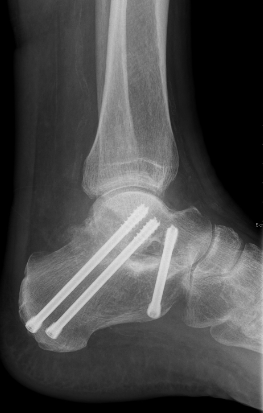

Gesamtes Spektrum der Fuß und Sprunggelenkchirurgie (Plattfuß, Spreizfuß, komplexe Vor-, Mittel- und Rückfußkorrektur, Krallenzehen und Hallux valgus/rigidus, Morton Neurinom)